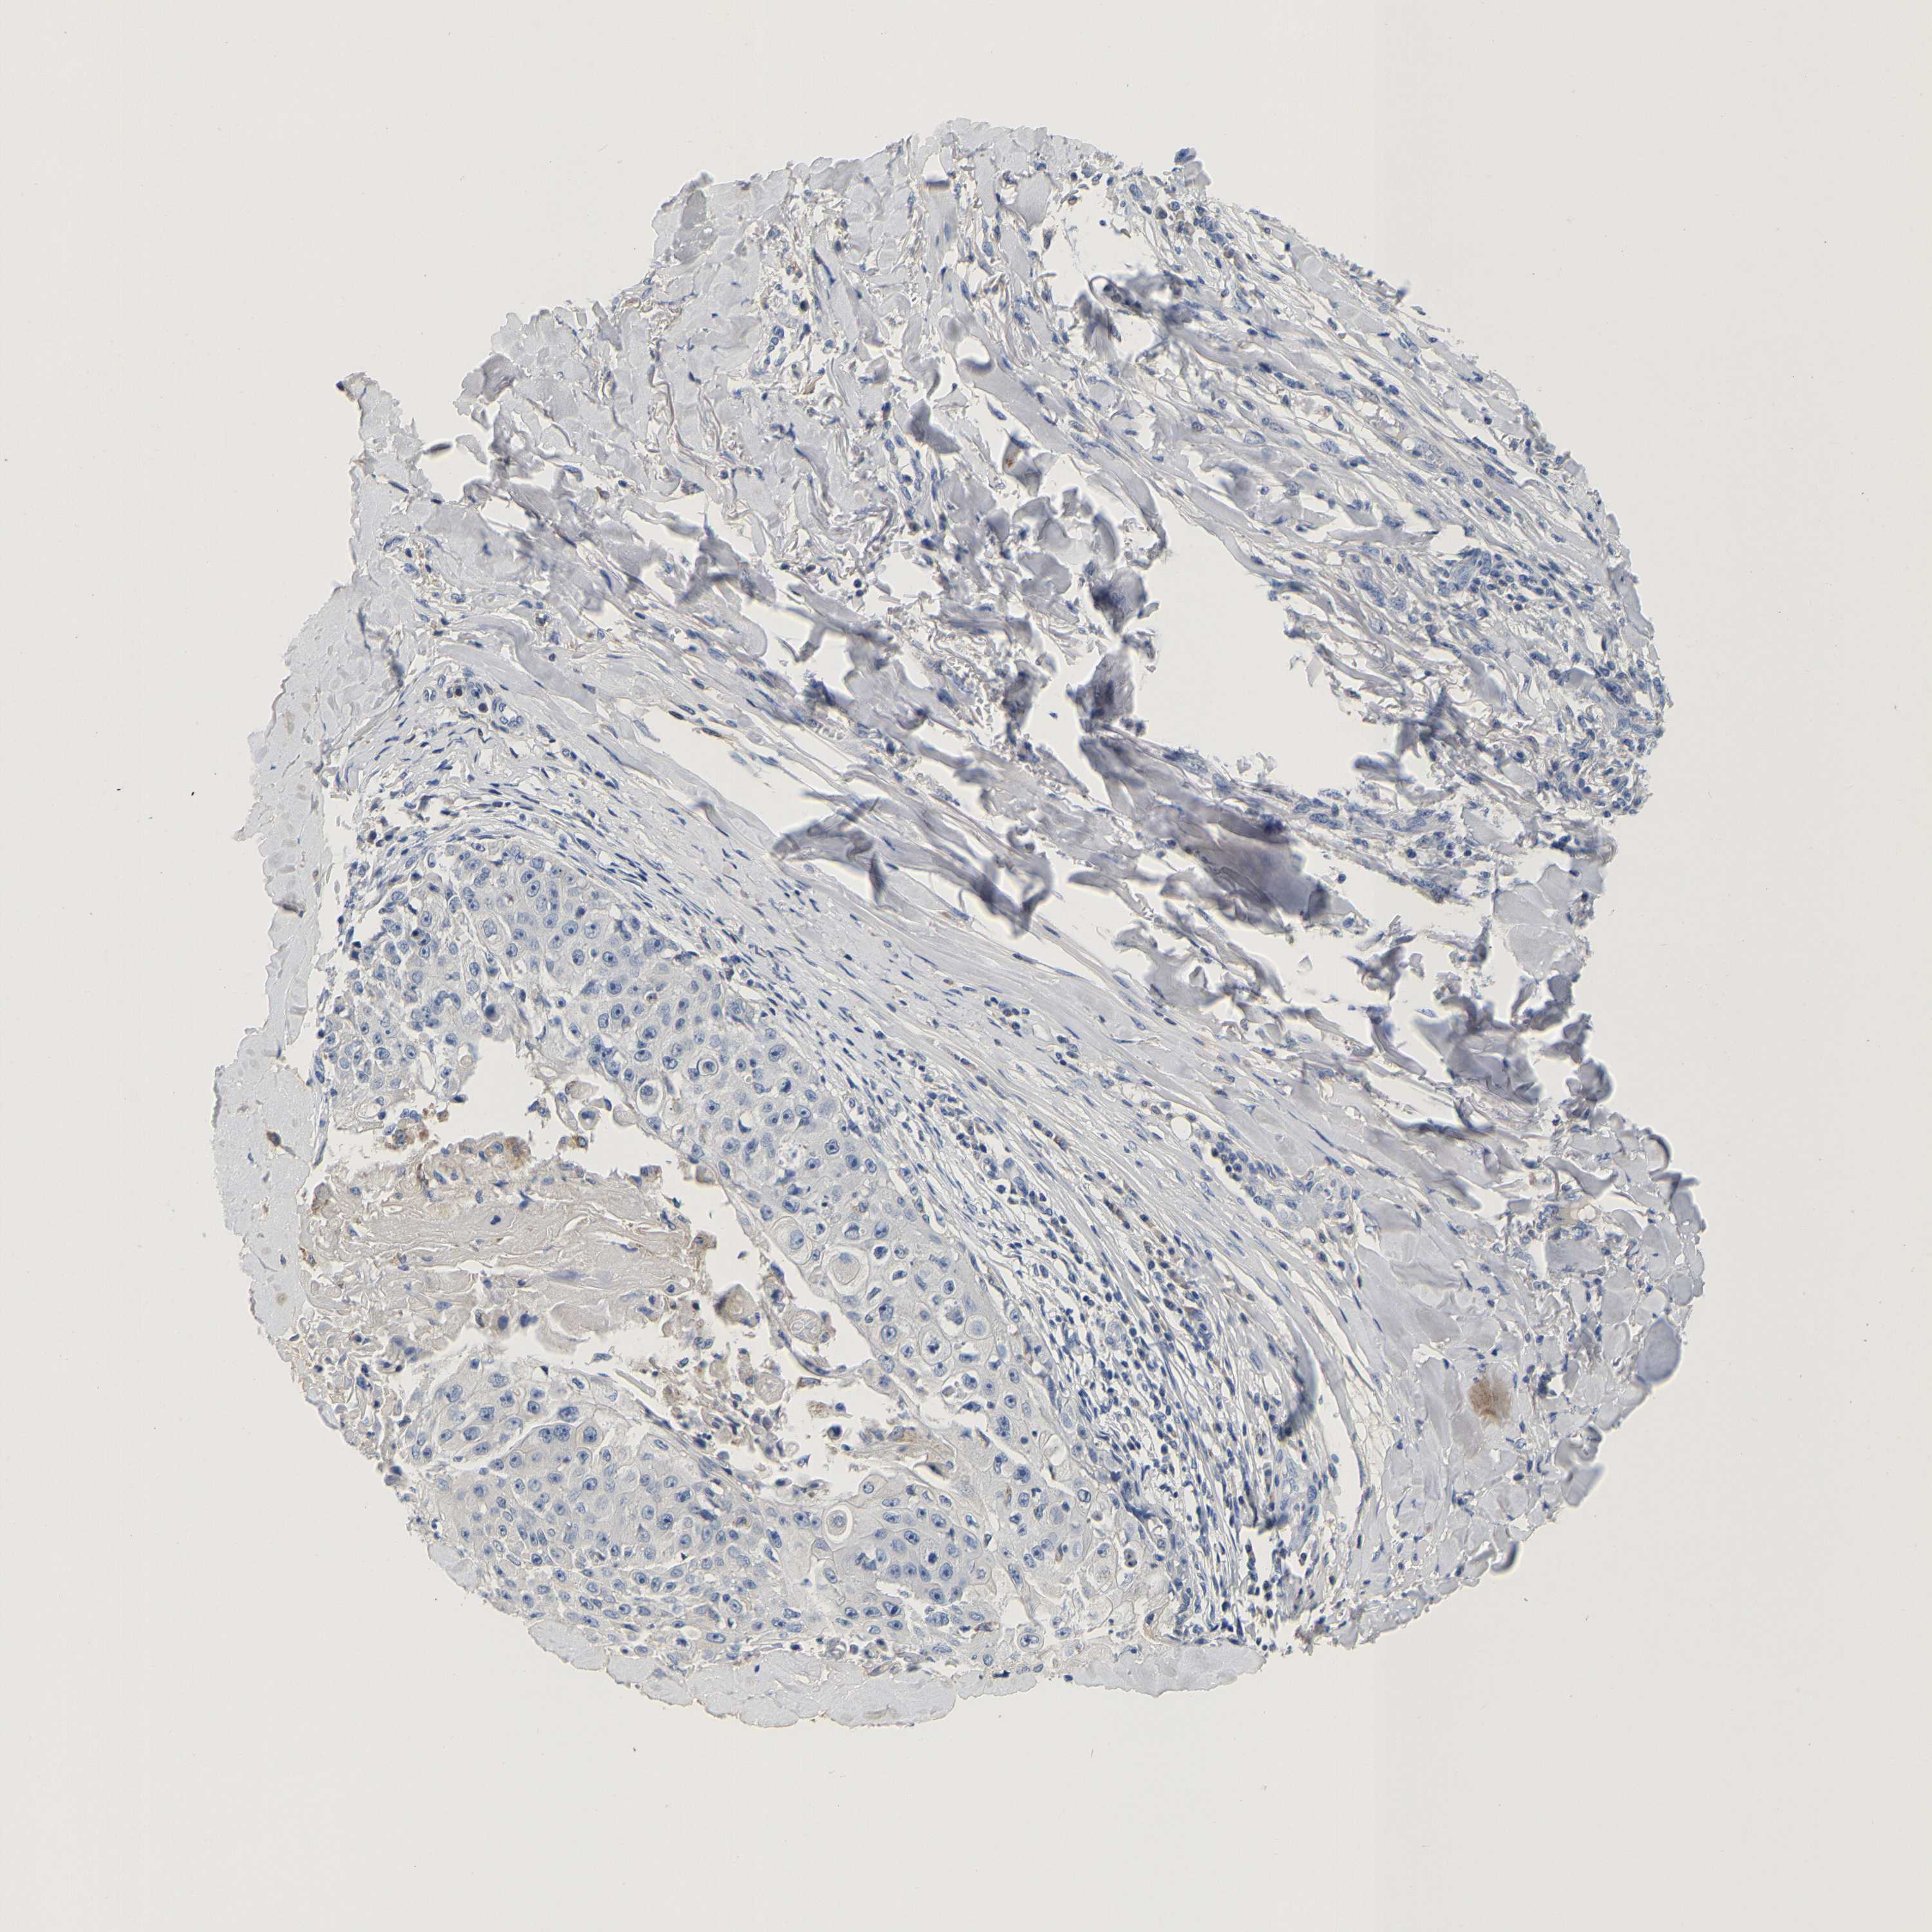

SKIN CANCER - Protein expressioni

A mouse-over function shows sample information and annotation data. Click on an image to view it in a full screen mode. Samples can be filtered based on level of antibody staining by selecting one or several of the following categories: high, medium, low and not detected. The assay and annotation is described here.

Antibody stainingi

Antibody staining in the annotated cell types in the current human tissue is reported as not detected, low, medium, or high, based on conventional immunohistochemistry profiling in selected tissues. This score is based on the combination of the staining intensity and fraction of stained cells.

Each image is clickable and will lead to virtual microscopy that enables deeper exploration of all samples and also displays staining intensity scores, fraction scores and subcellular localization as well as patient and tissue information for each sample.

Antibody HPA051162

Basal cell carcinoma

Squamous cell carcinoma, NOS

Squamous cell carcinoma, metastatic, NOS

Squamous cell carcinoma in situ, NOS